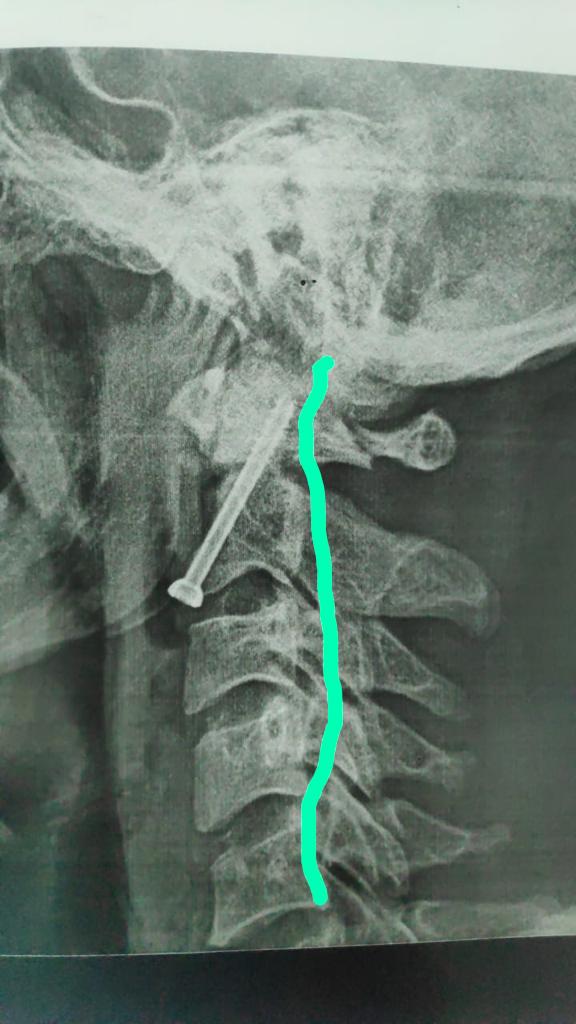

أكد الدكتور مصطفى عبد الخالق القائم بأعمال رئيس جامعة سوهاج أن فريق طبي متخصص من قسم جراحة العظام بالمستشفى الجامعي نجح في إجراء عملية جراحية لتثبيت كسر بالفقرة العنقية الثانية لشاب في العقد الثلاثين من عمره، وذلك بواسطة التدخل الجراحي من الأمام.

وقال "عبد الخالق" أن تلك الجراحة تعد من أكثر جراحات العمود الفقري خطورة نظرا لقربها من قاع المخ والحبل الشوكي وتحتاج إلى دقة ومهارة عالية في إجراؤها.

وأوضح الدكتور حمدي سعد مدير المستشفى الجامعي أنه بعد إجراء الفحوصات والإشاعات اللازمة للمريض تبين وجود كسر في الفقرة الثانية من العمود الفقري الرقبي، ويحتاج إلى جراحة عاجلة لتثبيت الفقرة العنقية، حيث كان هذا الكسر يشكل خطرًا كبيرًا على النخاع الشوكي وحياة المريض.

وذكر الدكتور عبدالرحمن الشيخ رئيس قسم جراحة العظام أنه بعد دراسة الحالة في ضوء نتائج الفحوصات الطبية، تم اتخاذ كافة التدابير التحضيرية للعملية، لافتًا الي ان الفريق الطبي الذي إجري العملية الجراحية للمريض كان تحت إشراف الدكتور أحمد صالح أستاذ جراحة العظام والعمود الفقري، حيث تم تثبيت الكسر بنجاح، وبدأ المريض الحركة بحرية تامة بمفرده بدون اي وسائل مساعدة.